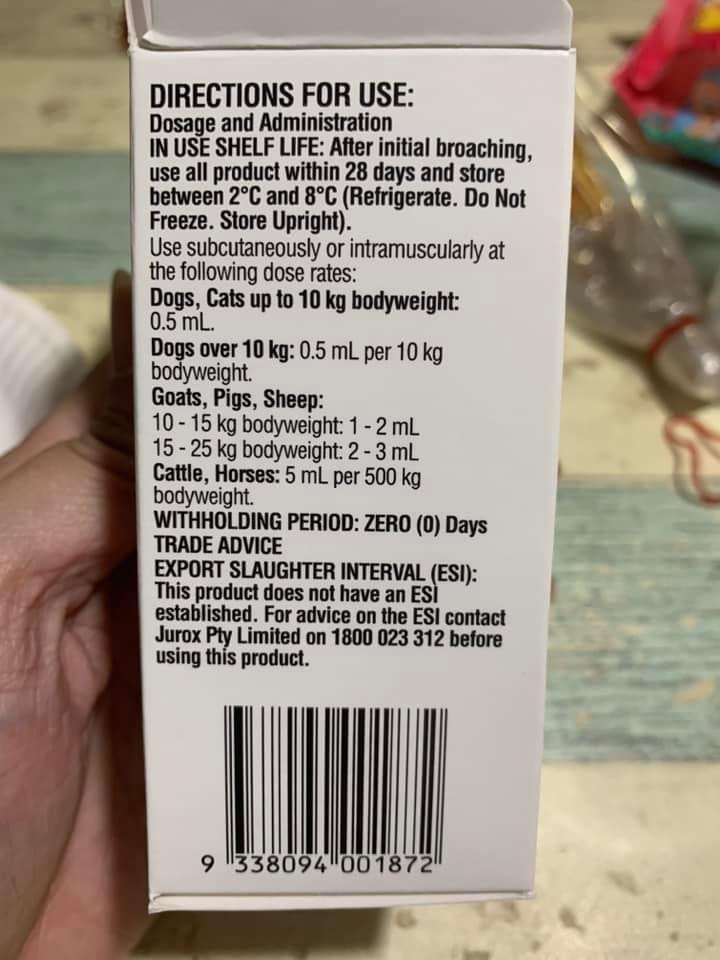

Noon:4.21kg, lose 70g in 3 weeks. Given Subcut, b12 b com jab, ornipural n niramine.

Morning: given Subcut n ornipiral n niramine jab. Did notice he drink water rather frequent, not after niramine

Morning; 4.75 5/10. Today I still didn’t start him on Niramine …

Night: today is his first niramine jab. he is a good boy when he knows I’m jabbing him.

Night: I still give niramine again. And ornipiral. Sayang him

Bought niramine for didi. Dosage stated 0.5ml, daily. Buy online says 1-2mg per cat that’s 0.1-0.2ml only. Side effect: may cause issue for cat w UTI. Tmr I start giving 0.1ml low dose see how.

Morning: bring didi go dr nally review. 4.28kg – lose 60g in 2 days. Cbc taken. HCT up to 30.4%, EOS even higher. Reject doing liver panel. Nothing significant. Just tell me to finish up the 14 days Clav then can stop (till 2.7) Drontal n review every 2-3 months. I’ll decide again Re the allergy jabs.